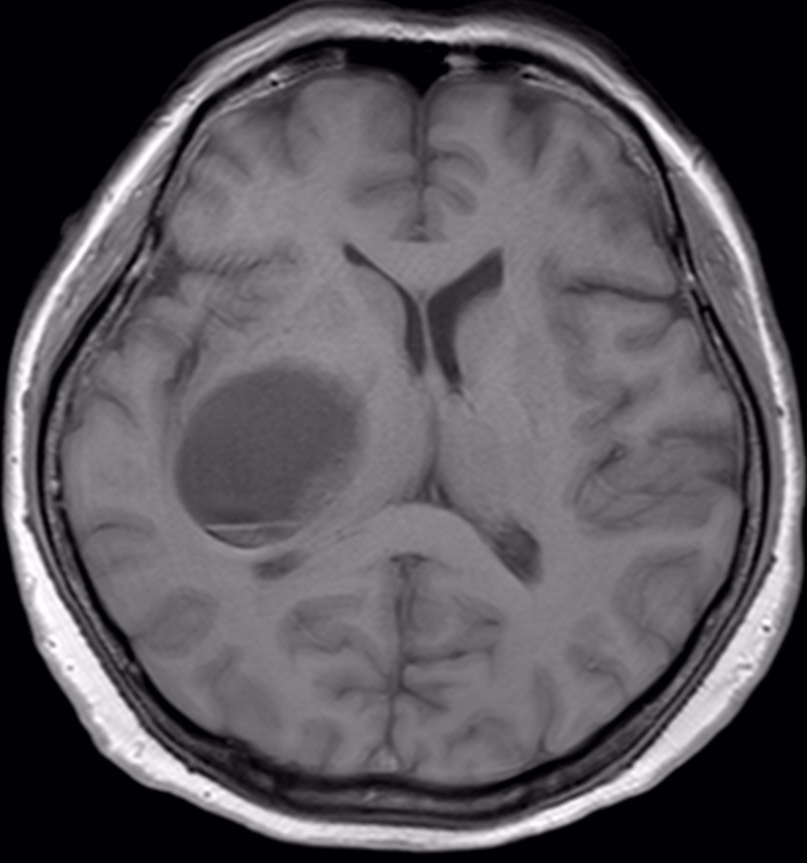

| Imaging:(Click to enlarge) | MRI示右侧基底节异常信号,T1等低信号,T2高信号,增强可见明显强化,考虑高级别胶质瘤。 |